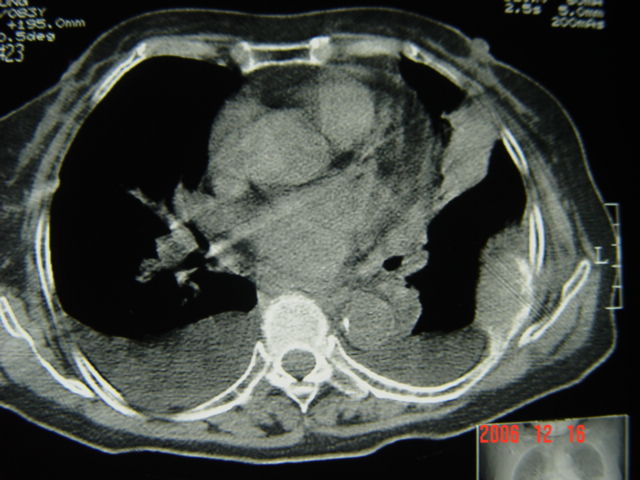

标题: CT5663:女、83岁,轻微咳嗽、左下胸痛。 [打印本页]

标题: CT5663:女、83岁,轻微咳嗽、左下胸痛。

左第八肋腋侧呈膨胀性骨质破坏,内侧见软组织密度肿块。左肺舌段呈楔形实变,基底近胸壁,尖端向肺门。双侧胸壁后缘见新月形水样密度区。

考虑:1、左第8肋骨转移瘤;

2、左肺舌叶肺栓塞可能性大;

3、双侧中量胸腔积液。